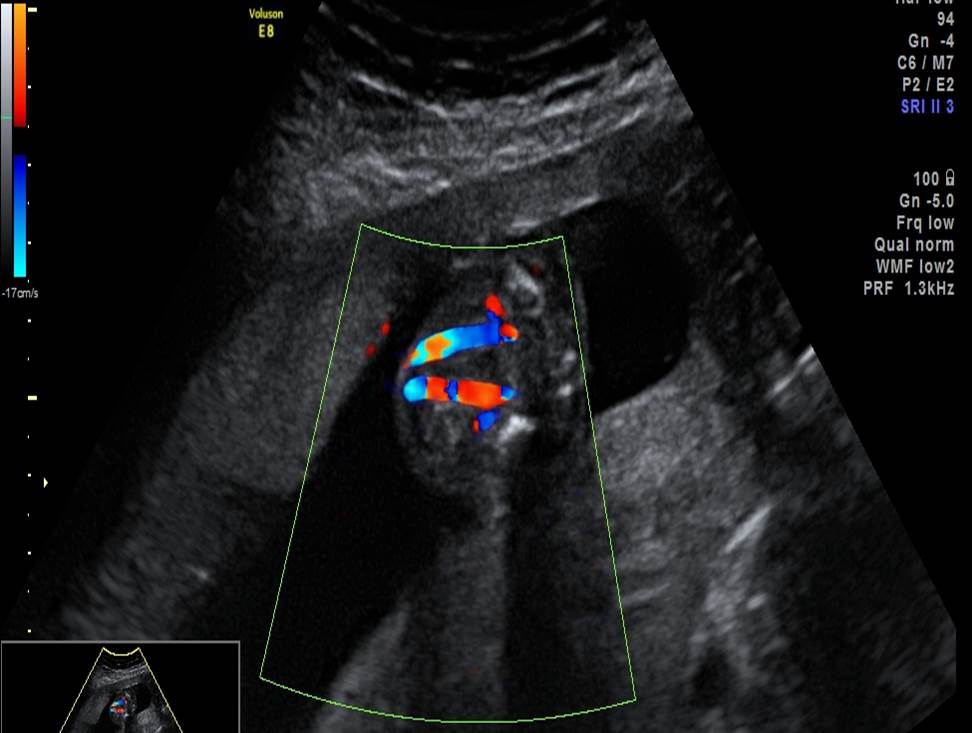

- Проанализируйте изображения плода в 22 недели, есть ли у него какие-либо маркеры хромосомной патологии?

- Необходимо ли рекомендовать инвазивную диагностику? Пациентке 30 лет, в 1 триместре комбинированный риск по трисомии 21 — 1:1200